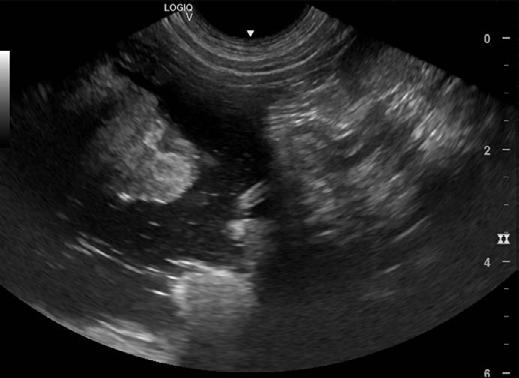

An abdominal ultrasound was performed on Thursday 11th April. The ultrasound showed an area of stomach wall that was thickened up to 2cm in places, with hyperechoic tissue causing loss of stomach wall layering in the region of the thickening. No other abnormalities were seen on ultrasound. Abdominal radiographs were also taken but did not show anything not visible on ultrasound.

2. Ultrasound images showing loss of layering and profound thickening of a portion (stars) of the gastric wall